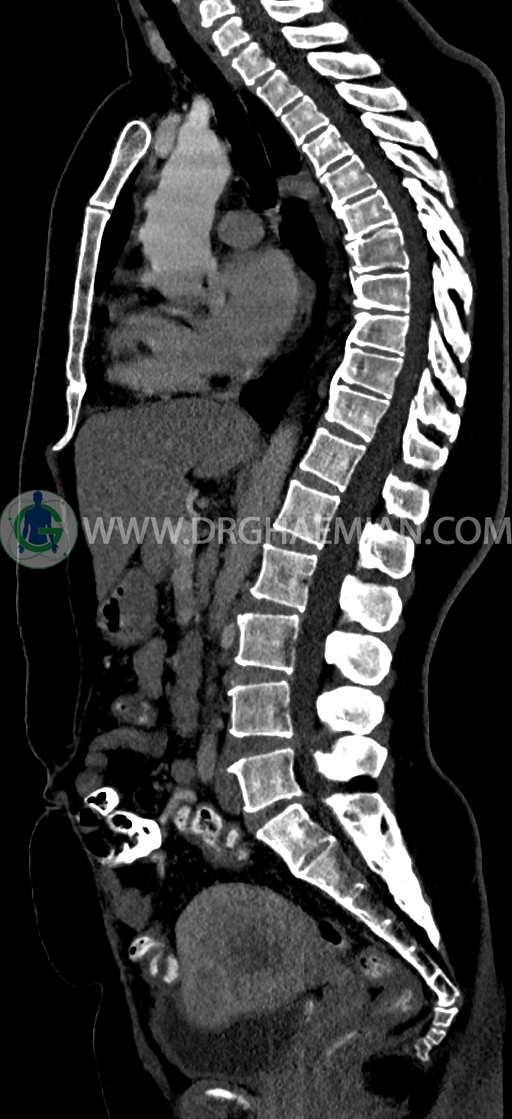

–lumbosacral transitional vertebrae